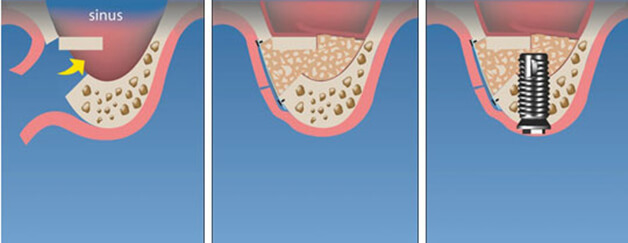

На верхней челюсти операция по восполнению недостающей высоты кости в боковых отделах в области гайморовых пазух называется синус-лифтинг. Бывает 3-х видов:

- Закрытый (вертикальный, малый) синус-лифтинг. Проводится в случае, когда массив костного материала в челюсти пациента достигает 7-8 мм в высоту. В некоторых ситуациях может быть выполнен одновременно с имплантацией. Но пациенту следует избегать немедленной нагрузки на новый корень — ее надо увеличивать очень аккуратно.

- Открытый (латеральный, большой) синус-лифтинг. Актуален при существенной атрофии кости, когда ее высота менее 7 мм. Наращивание проводят отдельно от имплантации, поскольку требуется достаточно много времени для приживления искусственной костной массы. Имплант ставится не раньше, чем через 20 недель после операции.

- Баллонная аугментация. Показана в случае большого дефицита костной массы. Метод напоминает закрытый синус-лифтинг, но в данном случае под слизистую оболочку вместо гранул помещают баллончик с жидкостью. По мере увеличения баллона в размерах происходит отслоение слизистой в щадящем режиме. Образовавшуюся полость заполняют искусственным костнопластическим материалом. Имплант устанавливают сразу после операции.

Еще один вид костной пластики — синуспак (антропластика). Метод предполагает:

- пластику альвеолярного отростка;

- заполнение повторно созданного объема синуса одним из биопластических материалов или их комбинацией.

В зависимости от применяемого костнозамещающего материала, сроки приживления составляют от 4-6 до 12-18 месяцев.

Пример клинического случая

Пациент в результате аварии получил травму, и потребовалась имплантация зубов. Вначале было проведено экспериментальное обследование и при помощи компьютерной томографии получены снимки челюсти. Затем хирург выполнил операцию по наращиванию и частичному замещению костной ткани — закрытый синус-лифтинг с одномоментным вживлением 4-х имплантов.

Через месяц выполнено временное протезирование. Спустя еще 6 месяцев сделали контрольный рентгеновский снимок челюсти пациента для подтверждения приживления новых тканей и искусственного корня. В завершение стоматолог установил постоянные металлокерамические коронки, имитирующие натуральные зубы (изготовление заняло не более 2-х недель).